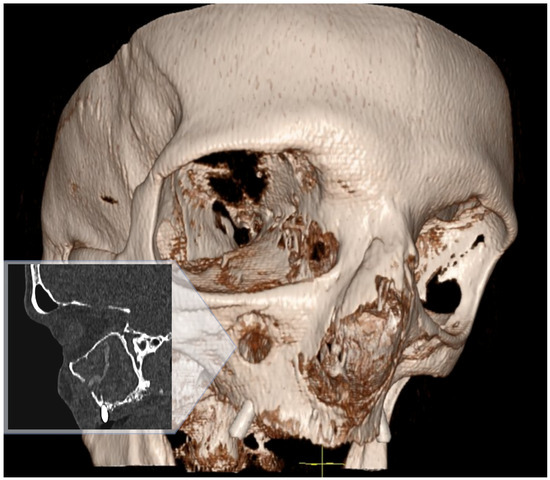

Background: Meningoencephalitis is a complex inflammatory condition of the CNS that can result in significant morbidity and mortality in critically ill adults. Accurate and timely neuromonitoring is essential for guiding management and improving outcomes. This study aimed to descriptively evaluate the prognostic value of early TCCD monitoring, particularly the pulsatility index, and its integration with conventional and perfusion MRI in patients with meningoencephalitis. Methods: We present an observational, retrospective, cohort study involving ten adult patients (median age 56 years, IQR 45.5–68.5; mean 55.9, range 35–76) with neurological syndromes caused by suspected or confirmed infectious meningoencephalitis. Etiologies included bacterial meningitis/meningoencephalitis (50%), viral meningoencephalitis (10%), neurotoxoplasmosis (10%), progressive multifocal leukoencephalopathy (10%), and undetermined origin (20%). Patients underwent TCCD and MRI within 24 h. In five cases, standard MRI sequences were acquired, while in the remaining five, perfusion imaging was performed using Arterial Spin Labelling (ASL). A favorable outcome was defined as survival with neurological recovery (Glasgow Outcome Scale > 5) at ICU discharge. Results: TCCD-derived PI provided valuable information on cerebral hemodynamics. PI values ≤ 1.25 were associated with favorable clinical outcomes and symmetrical MRI findings. Conversely, PI > 1.25 correlated with poor prognosis and often preceded MRI-detectable structural damage. When combined with ASL, PI mirrored the detected perfusion asymmetries and was associated with poor prognosis in fatal cases. Conclusions: Bedside TCCD can offer real-time assessment of cerebrovascular dynamics and, when integrated with conventional and ASL MRI, could enhance the understanding of pathophysiological processes in meningoencephalitis, supporting timely and informed decisions in neurocritical care.